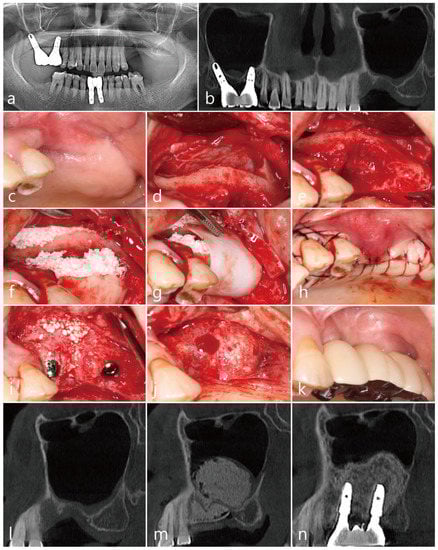

The patient was a 65 years old nonsmoking male, who visited the clinic for the treatment of a failed implant and re-implantation. The patient did not have any systemic diseases that could interfere with the operation, except for hyperlipidemia. A preoperative panoramic radiograph revealed severely resorbed bone around #15 (Figure 3a). On the panoramic image of the CBCT before the surgery, pneumatization of the left maxillary sinus was observed. In addition, severe bone resorption due to the fact of peri-implantitis was observed on the distal aspect of the #24 implant (Figure 3b). On the preoperative coronal CBCT scan, the buccal bone of the #15 tooth was severely resorbed (Figure 3c), and the residual bone height of the left posterior molar site was significantly reduced (Figure 3d). PSAAs were observed on both lateral sinus walls. On the right, the diameter of the PSAA was 1.5 mm, and the vertical position was 7.3 mm from the floor of the right maxillary sinus. On the left, the diameter of the PSAA was 1.3 mm, and the vertical position was 11.2 mm from the floor of the left maxillary sinus (Table 1).

After removal of the old prosthesis, the #15 tooth was extracted under local anesthesia with 2% lidocaine (containing 1:100,000 epinephrine) (Figure 3e). The mucoperiosteal flaps were reflected, followed by a lateral window preparation for MSA. The lateral sinus bony window was obtained, and the sinus membrane detached from the sinus floor without perforation. The severe bone defect around the extraction socket of the #15 tooth was observed (Figure 3f). Sinus bone augmentation was performed using an Osteon III (particle size 0.5–1.0 mm; Genoss Co., Ltd., Suwon, Republic of Korea), and implants (Implantium, Dentium Co., Ltd., Suwon, Republic of Korea) were placed. A mesial bony defect was observed around the implant during the procedure (Figure 3g) and was filled with Osteon III (particle size 0.2–0.5 mm; Genoss Co., Ltd., Suwon, Republic of Korea) (Figure 3h). The obtained lateral sinus bony window was placed on the bony defect without fixation after slight trimming to match the size and shape of the defect (Figure 3i). The surgical site was covered with a resorbable collagen membrane (Genoss Co., Ltd., Suwon, Republic of Korea) (Figure 3j). The mucoperiosteal flaps were closed with 5-0 nylon. The healing was uneventful, and the wound was not exposed (Figure 3k). The uncovering procedure was performed six months after the surgery. The grafted lateral window bone was well integrated with the surrounding bone (Figure 3l). Healing abutments were inserted, and the flaps were closed. After two months, the final prosthesis was delivered (Figure 3m).

On the same day, lateral MSA and implant placement were performed in the left maxillary posterior region. Under local anesthesia with 2% lidocaine (containing 1:100,000 epinephrine), the mucoperiosteal flaps were reflected. The implant placed in the #24 site was explanted, and a lateral sinus window site was prepared for MSA. The extraction socket of the #27 tooth had a wide-deep defect (Figure 3n). The MSA using an Osteon III (particle size 0.5–1.0 mm; Genoss Co., Ltd., Suwon, Republic of Korea) was performed, and three implants were placed (Table 1). A buccal bony defect was observed around the #27 implant site (Figure 3o). After filling the bony defects with Osteon III (particle size 0.2–0.5 mm; Genoss Co., Ltd., Suwon, Republic of Korea), the obtained lateral sinus bony window was positioned in the #27 implant site (Figure 3p). The surgical site was covered with a resorbable collagen membrane (Genoss Co., Ltd., Suwon, Republic of Korea) (Figure 3q), and the flaps were closed with 5-0 nylon (Figure 3r). Antibiotics (ciprofloxacin; 500 mg; Ildong Pharmaceutical Co., Ltd., Seoul, Republic of Korea) and a nonsteroidal anti-inflammatory drug (Etodol; 200 mg; Yuhan Co., Ltd., Seoul, Republic of Korea) were prescribed for two weeks. The healing was uneventful. The uncovering procedure was performed six months after the surgery. The buccal bony defects around the #27 implant were resolved, and the transplanted lateral sinus window was well integrated with the surrounding native bone (Figure 3s). The bone above the cover screw was removed using a round surgical bur (Figure 3t). The prosthesis was delivered after two months (Figure 3u).

The sinus augmented bone obtained from the MSA was well integrated on the coronal images of the CBCT performed six months after the final prosthesis was delivered (Figure 3v,w).

Figure 3. Case 3: (a) preoperative panoramic radiograph; (b) preoperative panoramic image of the CBCT scan; (c) posterior superior alveolar arteries (PSAAs) are shown on the coronal images of the preoperative CBCT scans on both sides; (d) coronal image of the preoperative CBCT scan showing a severely resorbed bone defect around the extraction site of the left maxillary second molar; (e) preoperative clinical view after extraction of the right maxillary second premolar; (f) after flap reflection, a lateral bony window was prepared for maxillary sinus augmentation; (g) a bony defect was observed after implant placement and sinus augmentation; (h) the buccal bony defect was filled with particulate bone graft; (i) the obtained lateral bony window was placed on the bony defect without fixation; (j) the surgical site was covered with a resorbable collagen membrane; (k) clinical view six months after surgery; (l) the lateral bony window was well incorporated with the surrounding native bone at six months after surgery; (m) clinical view after final prosthesis delivery; (n) after flap reflection, the #24 implant was explanted and a lateral bony window was prepared for maxillary sinus augmentation; (o) after sinus augmentation and implant placement, the buccal bony defects are shown; (p) after filling the buccal bony defect with particulate bone graft, the obtained lateral bony window was positioned on the bony defect; (q) the surgical site was covered with a resorbable collagen membrane; (r) the flaps were closed with minimal tension; (s) the uncovering procedure was performed six months after surgery, and the grafted lateral bony window was well integrated with the surrounding native bone; (t) the bone above the cover screw was removed with a round surgical bur, and after the healing abutments were inserted, the flaps were closed; (u) clinical view after final prosthesis delivery; (v) coronal CBCT image at six months after prosthesis delivery; (w) coronal CBCT scan showing the filling of the defect around the implant placed at the extraction site of the left maxillary second molar.